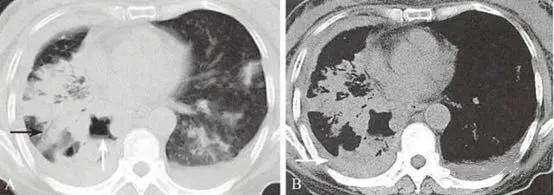

(2)周围型,肿瘤发生在段支气管以下,以腺癌较为多见。

CT易显示肿瘤内的空洞及钙化,空洞多不规则,壁厚薄不均匀,可见壁结节;钙化多为斑片状或结节状。

(3)弥漫型,肿瘤发生在细支气管或肺泡,弥漫分布于两肺。

两肺多发小结节或粟粒状结节,以中下肺为著,常伴有单侧或双侧的胸腔积液。结节大小不等,但每个结节的形态学表现与孤立性周围型肺癌具有相同的特征。